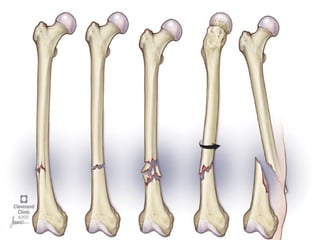

Fractures are breaks in the

continuity of the bone.

It usually occurs as a result of

high impact forces that cause

the bone to bend or twist.

3. Fracture

Impact and contact sports

often lead to fractures of the

bone (mostly arms, legs and

feet), all of which can be

painful, take weeks of

immobilization to heal and

may sometimes require

surgery to correct.

Fractures are an inherent risk

with most strenuous and/or

contact sports, but you can

reduce the risk by wearing

the appropriate padding,

warming up, working out to

keep muscles strong and

flexible, practicing good

technique, etc.

Also, don’t “play through

the pain,” as sometimes

the pain is a sign of a strain

or sprain that left

untreated can make the

bone vulnerable to

fracture.